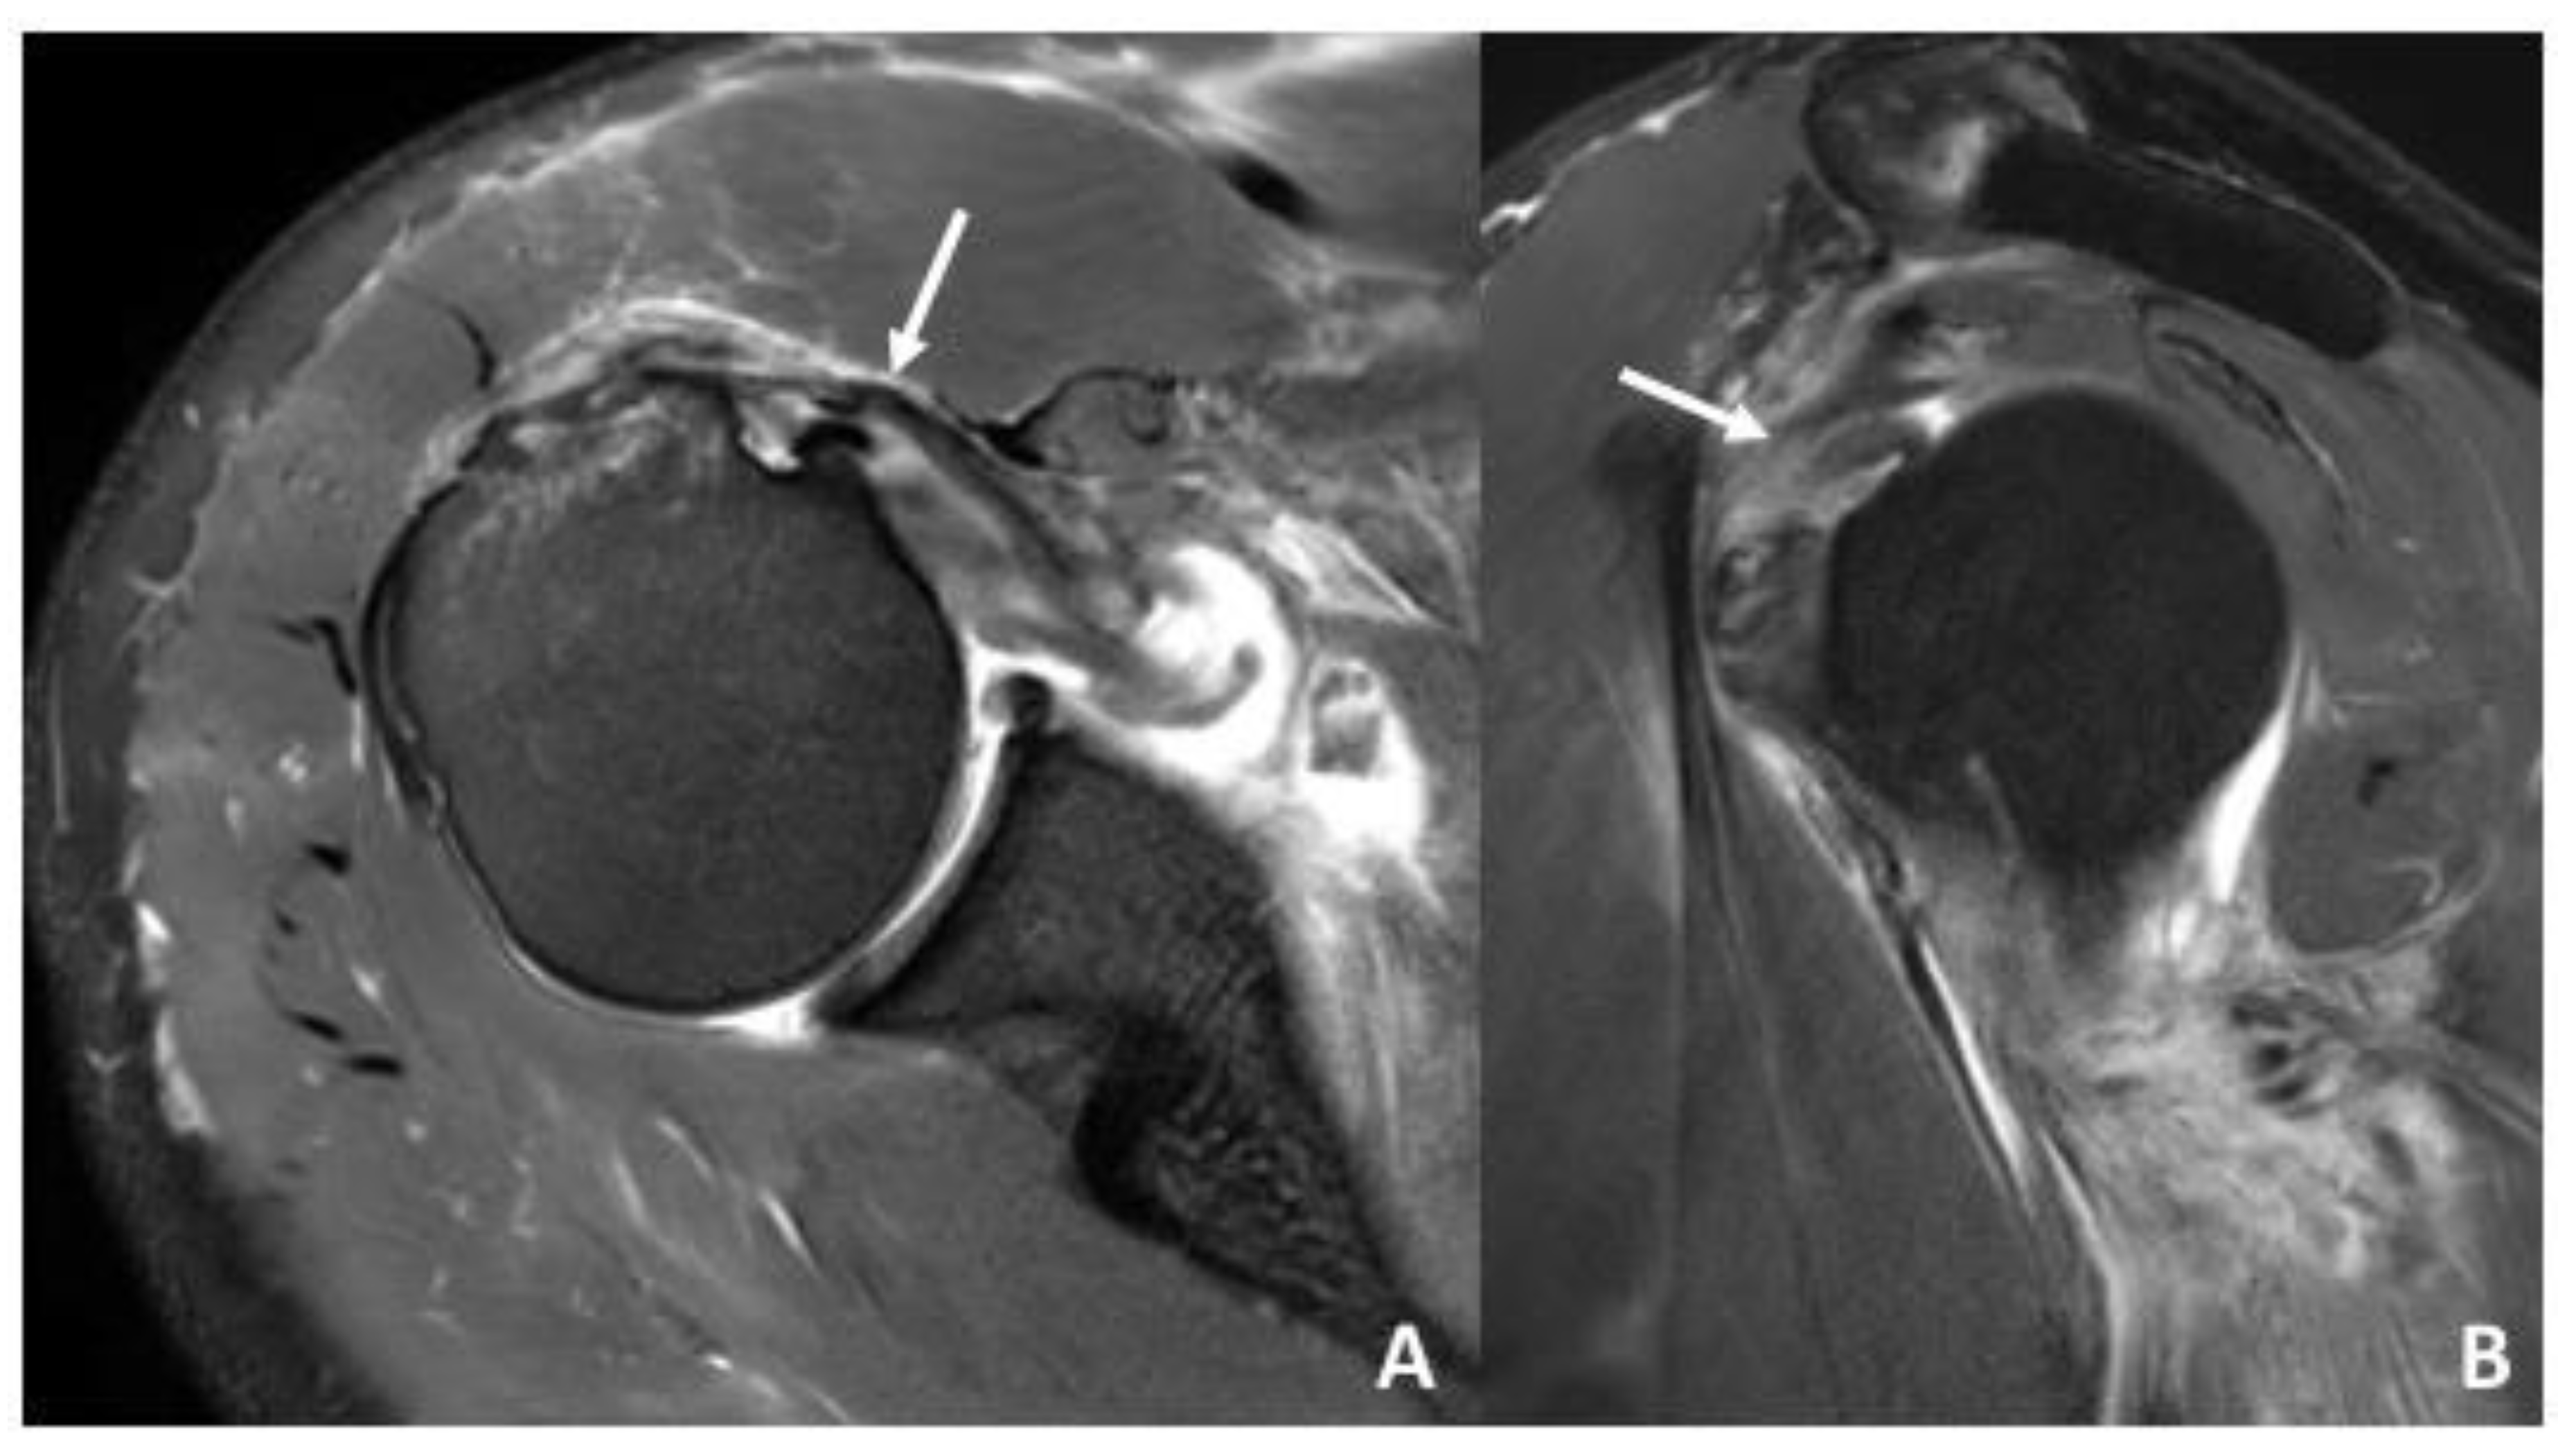

| Biceps pulley | Pulley Lesions graded according to Habermeyer et al. [8] | sGHLtear: 16 (48%) CHL tear: 12 (36%) sGHL and CHL tear: 11 (33%) |

| LHBT | Subluxation/dislocation of the LHBT | Subluxation: 4 (12%) Dislocation: 0 (0%) |